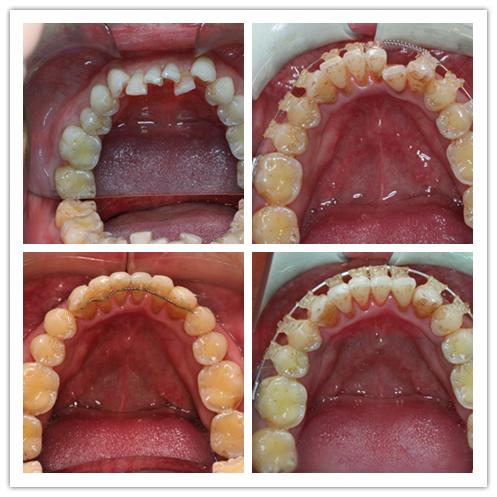

當患者經過初診篩查並決定進行矯正後,醫生將給患者做一系列檢查,以便制訂矯正計畫。首先,患者需要做乙肝表面抗原檢査,並拍全套牙齒x射線膠片。其次,主治醫生將為患者進行口腔檢査,取記存模型,照口內像、面像,保存患者的治療前資料。再次,主治醫生將與患者約定下次就診時間,與患者商談矯正計畫,在得到患者的同意後正式開始治療。這個階段需要1〜2周的時間。